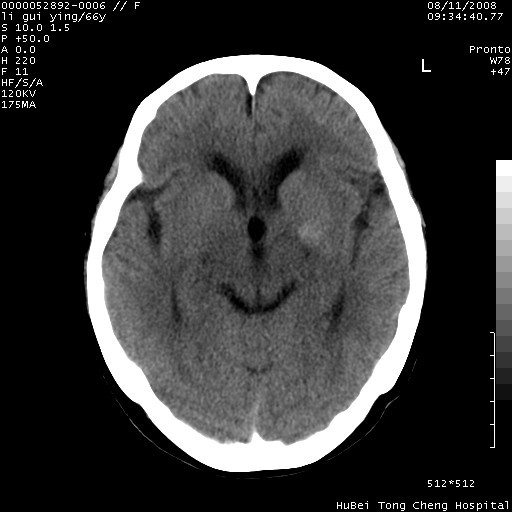

以下是引用yangyudong333在2008-8-12 12:22:00的发言:[br]1.病灶呈圆形[br]2.周围无水肿带[br]3.密度不均匀,内有点状钙化[br]4.无占位效应[br] 考虑良性占位性病变,血管瘤可能性大